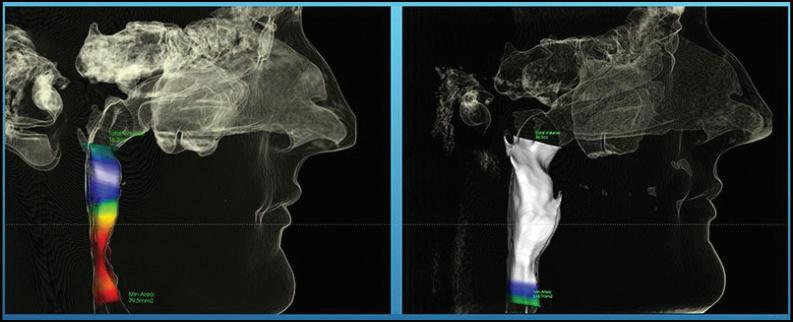

By Michael Rogers, DDS Fairlington Dental

Breathing is something most of us do without thinking, yet how we breathe has a significant impact on oral health and overall well-being. While the nose is designed to filter, warm, and humidify air, many people breathe through the mouth, particularly during sleep. Although it may seem harmless, chronic mouth breathing can contribute to dental problems, orthodontic issues, and broader health concerns.

Mouth breathing often occurs when nasal passages are blocked by allergies, chronic sinus issues, or enlarged tonsils and adenoids. In some cases, it can develop into a habitual pattern even after the original cause is resolved. To meet the body’s need for oxygen, the mouth takes over when nasal airflow is blocked. While this provides a short-term solution, persistent mouth breathing can create long-term challenges for oral health and overall wellness.

The Oral Health Connection

One of the most immediate effects of mouth breathing is dry mouth. Saliva plays a critical role in washing away bacteria, neutralizing acids, and protecting teeth from decay. Without sufficient saliva, the risk of cavities, gum disease, and bad breath increases. Over time, chronic dryness can make it difficult to maintain a healthy oral environment and may contribute to inflammation.